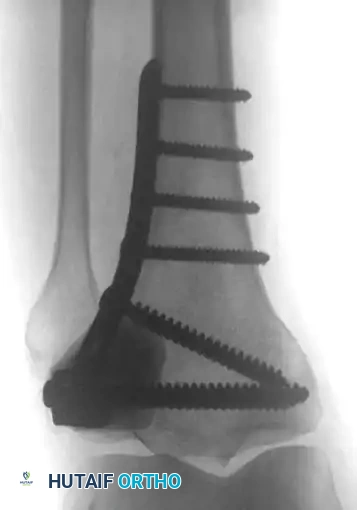

4. Curettage and Cementation of Distal Extremity Lesions

For lesions distal to the knee or elbow (e.g., distal tibia, ankle), where intramedullary nailing or massive endoprostheses are less feasible, extended curettage followed by defect packing with PMMA is highly effective. This technique provides immediate structural support and excellent pain relief.

Fig. 22-27: (A, B) Anteroposterior and lateral radiographs of the left ankle of a 78-year-old woman with metastatic kidney cancer. (C, D) Postoperative views after extended curettage and packing of the defect with methacrylate. The patient resumed immediate full weight-bearing with complete pain relief.